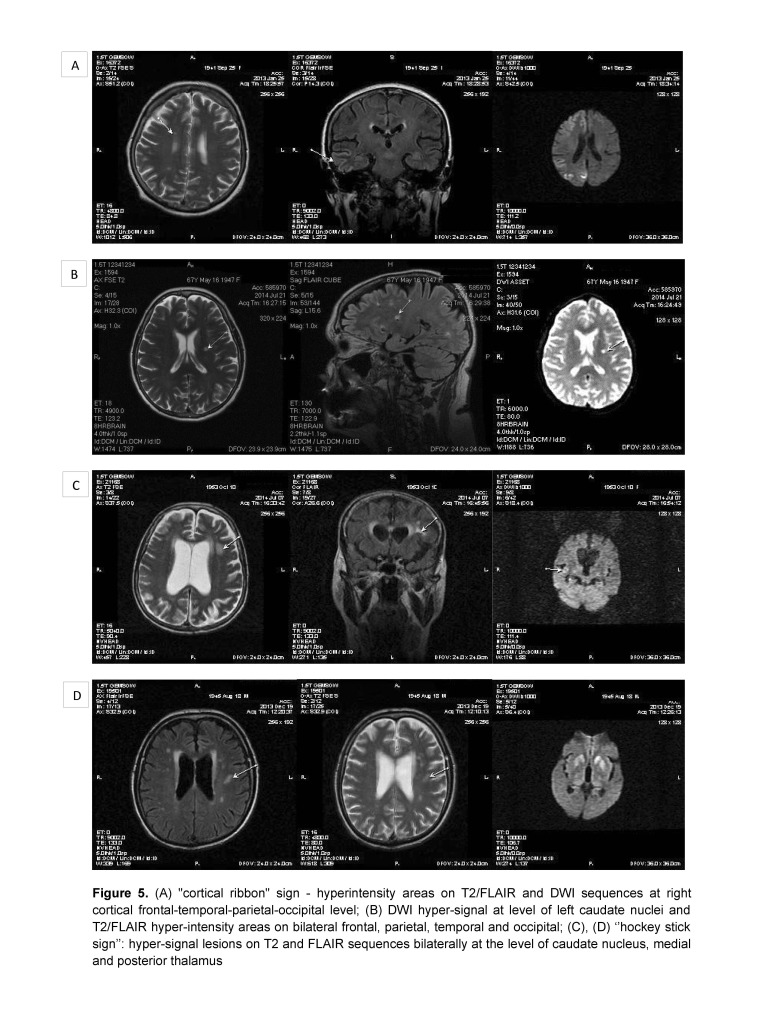

A 68-years-old man presented a progressive onset, approximately three months before admission, of cognitive decline, postural instability, dysarthria, dysphonia, and diplopia. In the last three weeks, the patient had been unable to maintain an upright position, in the last two days he had became unable to speak, eat, and had presented a motor deficit of the four limbs. Two years before, the patient had been diagnosed with Parkinson’s disease and was treated with levodopa-benserazide, but without improvement. The medication was stopped because of a hallucinatory episode that had been remitted afterwards. The neurologic examination revealed a clinical picture of akinetic mutism and myoclonus. The brain MRI showed high signal lesions on T2, FLAIR and DWI sequences bilaterally at the level of caudate nuclei, medial and posterior thalamus (aspect of “hockey stick” sign, and cortical frontal parasagittal (Fig. 1). Routine laboratory tests were within normal range. Cerebrospinal fluid examination showed normal glucose, 632 mg/ dl albumin (normal range <350 mg/ dl), 2 polymorphonuclears/ mm3. Protein 14-3-3 was positive in CSF (ELISA), amyloid β1-42 was normal (550 pg/ ml, normal range>450 pg/ ml, and tau protein was elevated (1640 pg/ ml, normal range <1300 pg/ ml). Serum anti-neuronal antibodies profile and anti-glutamate receptor antibodies were negative. Electroencephalography showed slow waves on the left frontal, temporal and parietal leads on a background slowing of the rhythm and after two months the EEG showed a loss of alpha background, generalized slowing in the theta band and no PSWC (Fig. 5A).

Fig. 5.

(A) “cortical ribbon” sign – hyperintensity areas on T2/ FLAIR and DWI sequences at right cortical frontal-temporal-parietal-occipital level; (B) DWI hyper-signal at level of left caudate nuclei and T2/ FLAIR hyper-intensity areas on bilateral frontal, parietal, temporal and occipital; (C), (D) “hockey stick sign”: hyper-signal lesions on T2 and FLAIR sequences bilaterally at the level of caudate nucleus, medial and posterior thalamus